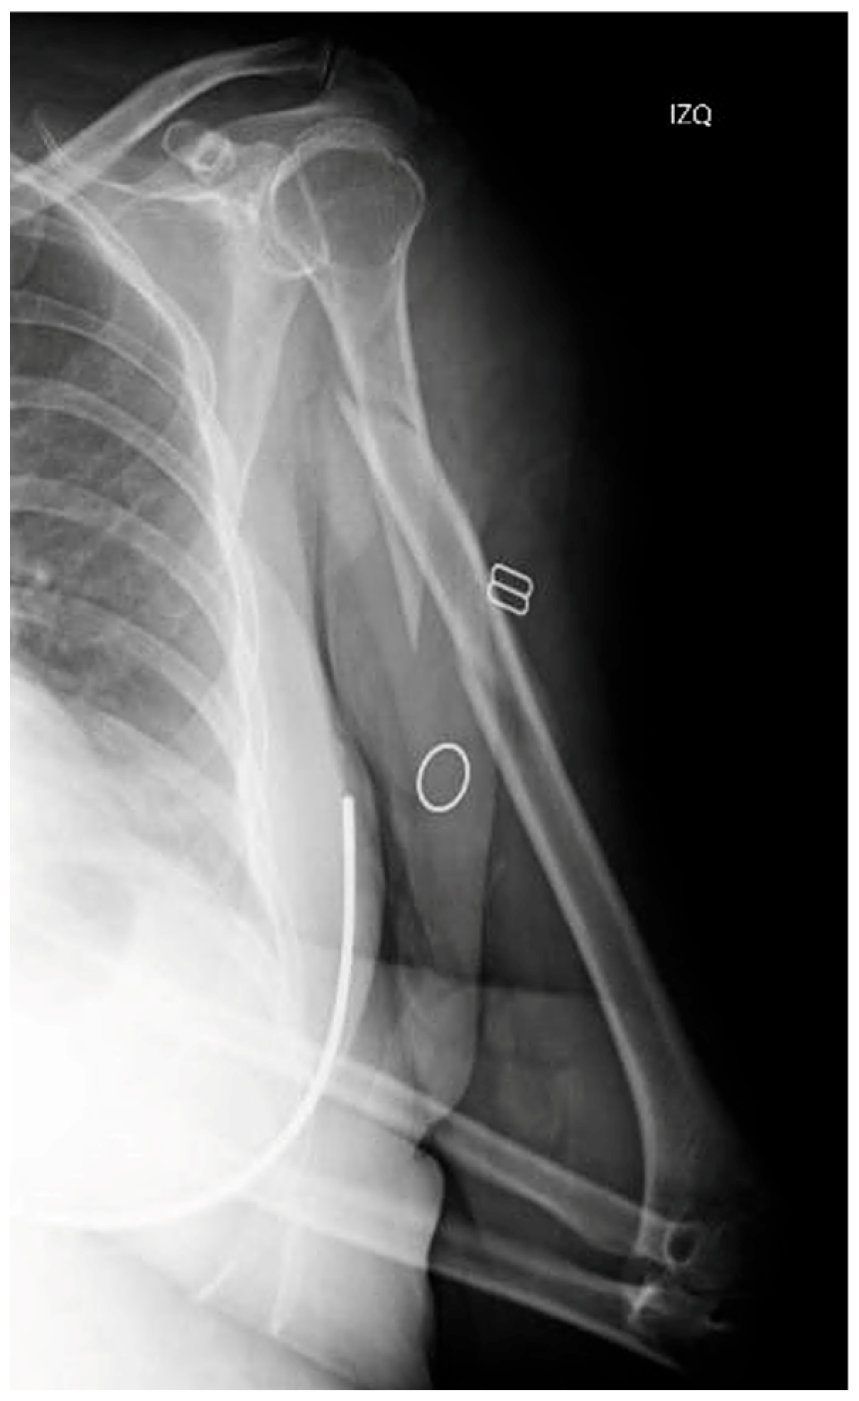

Two weeks after surgery, the patient achieved 100° flexion and −15° extension, without any kind of secondary displacements being radiographically apparent. At three months, X-rays demonstrated that healing was progressing satisfactorily, with the patient exhibiting a normal range of motion. The 6-month radiographs showed complete healing of the fracture, with the physical exam revealing a full range of motion. At one year from the procedure, function was assessed by means of the Disabilities of the Arm, Shoulder and Hand (DASH) scale and the Mayo Elbow Performance Score (MEPS), in which the patient obtained scores of 86 and 75 points, respectively (Figure 5). Simultaneously, the patient was referred to Rheumatology due to a low-energy fracture and a history suggestive of bone fragility. Osteoporosis was confirmed, and treatment with calcium, vitamin D, and antiresorptive therapy was initiated.

Figure 5. Radiographic follow-up at 6 months post-op.